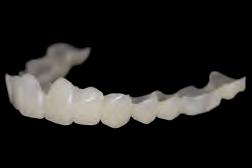

Prettau 3 Dispersive zirconia

Prettau Dispersive zirconia materials are, according to their manufacturer Zirkonzahn, characterised by a smooth, natural colour gradient built into the manufacturing process, offering a triple gradient of natural colour, translucency and flexural strength. The company says this is thanks to a special technique that does not blend colours into layers but disperses them evenly and that, with the Gradual-Triplex-Technology, a triple gradient has been developed for the new Prettau 3 Dispersive zirconia. Zirkonzahn also says that in addition to the colouring smooth gradient, translucency and flexural strength levels also change. Whereas the incisally increasing translucency results in a highly translucent incisal edge, the cervically increasing flexural strength results in an extremely high flexural strength at the tooth neck, according to the company. Accordingly, Prettau 3 Dispersive can be used for all kinds of zirconia restorations, although it is particularly suitable for monolithic rehabilitations. For a final prosthesis with a colour matching with the patient’s natural tooth shade, Zirkonzahn says their new shade guides can be used. Composed of monolithic zirconia sample teeth, they exist for all Prettau Dispersive zirconia materials and are available in the shape of a premolar as well as lower and upper incisor (also with minimal cutback for a totally customised shade guide). If the final restoration is milled out of a Prettau Dispersive zirconia blank identical to the one of the shade guide used, the company says the colour of the zirconia restoration corresponds 1:1 with the natural tooth shade of the patient.

Monolithic maxillary restoration made with Prettau 3 Dispersive zirconia (13-23).